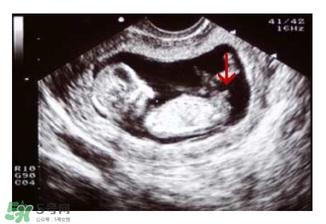

主要通过尾椎那里判断。 为了让大家更直观一些,我找两个比较明显的图,男左女右,大家看男孩儿的特征点与身体呈45度角,还多一些,而女孩儿的特征点几乎和躯体平行。图第一张男宝,第二张女宝

用线条表示一下就更直观了.当然,这也不是完全绝对的,如果你们发现自己的宝贝儿与心想的不一样,那这理论不一定对,不是绝对的.千万不要因为这个而影响自己孕期心情,宝宝健康是第一位的,我只是把自己所了解到的知识给大家普及一下。